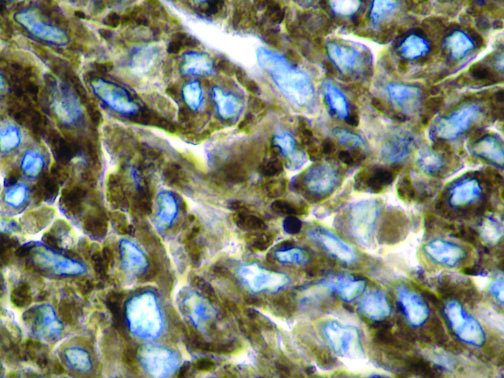

This activation induces inflammatory monocytes to highly express IL-6, starting a localized and then systemic cascade effect that results in hyperproduction of IL-6, which accelerates the inflammatory process. Because IL-6 also increases vascular permeability, excessive levels cause blood vessels to become very leaky. This, along with clotting factors released from vascular endothelial cells, stimulates the coagulation cascade, resulting in microthrombosis (tiny clots), which leads to ischemia and tissue death of the kidney, intestines, heart, liver, brain and extremities.